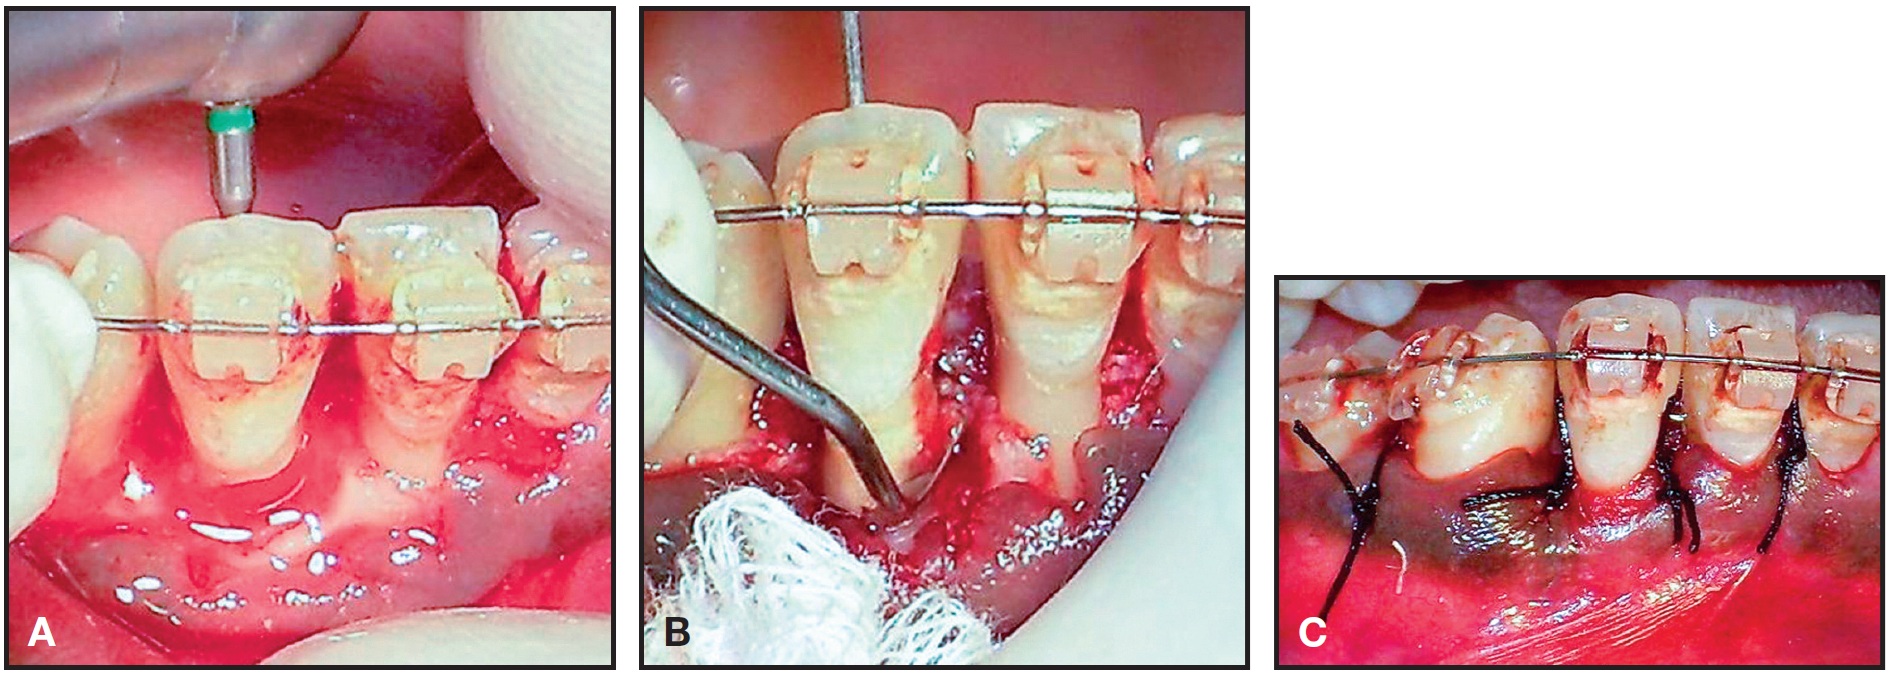

At this point, orthodontic treatment was interrupted so that periodontal therapy could be initiated. A buccal flap was raised to allow access to the injured root zone for open curettage of the EIRR (Fig. 5).

Fig. 5 Buccal flap raised for open curettage of lateral-incisor EIRR.

Since the curettage showed pulpal involvement in addition to the cementum and dentin resorption gaps, a root-canal treatment was performed (Fig. 6A). The root resorption gap was then sealed with glass ionomer cement (Fig. 6B), and the flap was closed with interdental sutures (Fig. 6C).

Fig. 6 A. Root-canal therapy of lower right lateral incisor. B. Resorption gaps sealed with glass ionomer cement. C. Flap closure with interdental sutures.